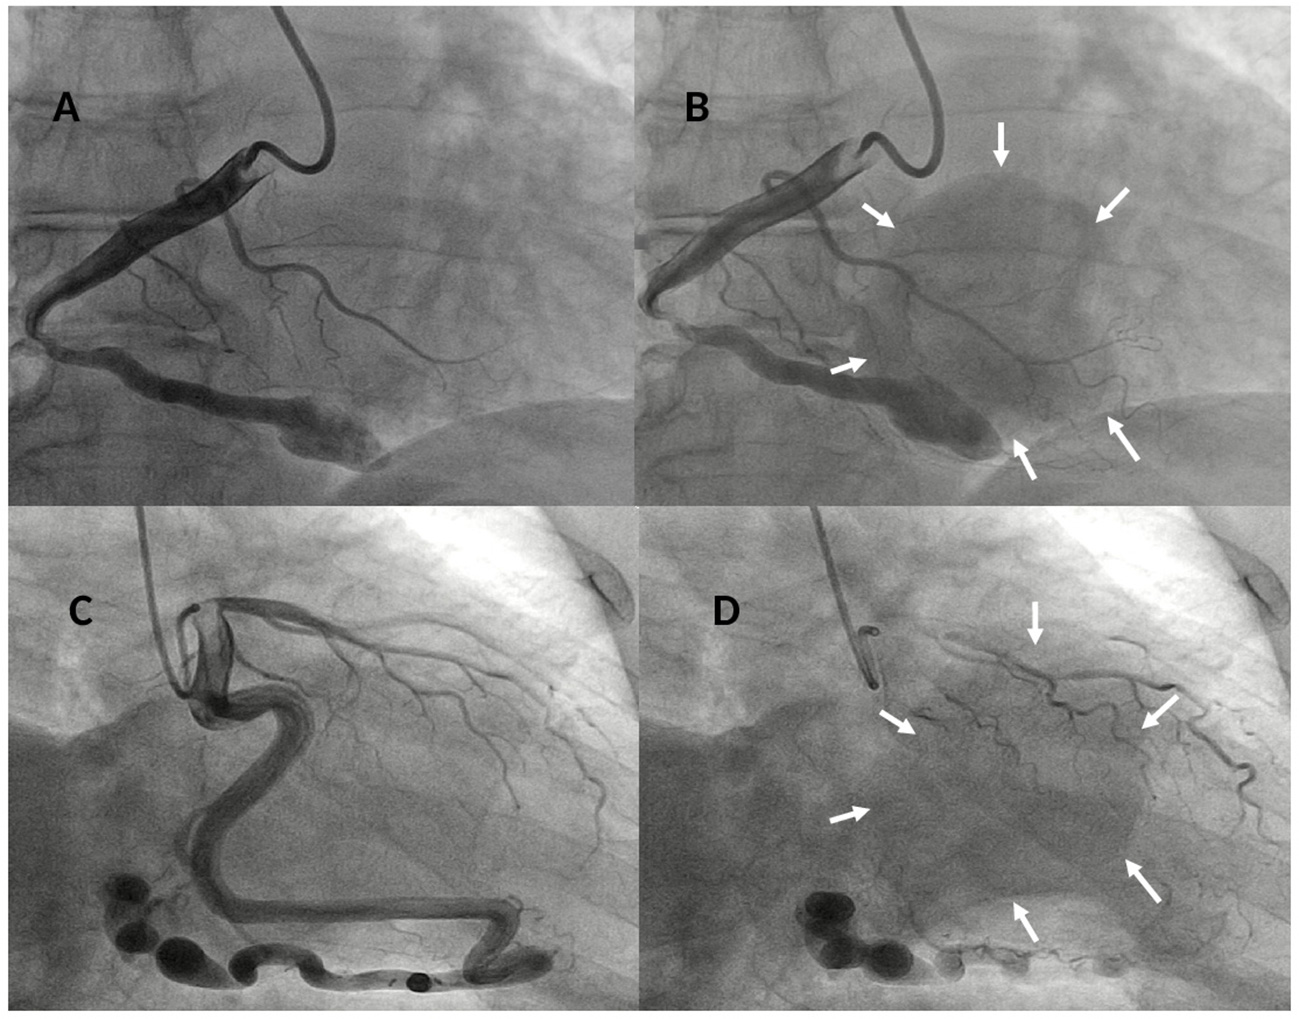

Figure 3

Baseline right coronary angiogram in LAO 30°- caudal 8° view showing a dilated and tortuous coronary artery (A) draining in a large round-shaped chamber (yellow arrows) within the right ventricle (B) confirming the diagnosis of a right coronary cameral fistula. Baseline left coronary angiogram in RAO 15°- caudal 25° view showing a giant and very tortuous left circumflex (LCx) coronary artery (C) draining through a fistulous path in a large round-shaped chamber (yellow arrows) within the right ventricle (D) confirming the diagnosis of a left circumflex coronary cameral fistula.

The patient underwent cardiac catheterization and selective coronary artery angiography in multiple projections showing severely dilated and tortuous RCA and LCx draining distally in a large round-shaped chamber within the RV (Figure 3, Supplementary Videos 2, 3) confirming the diagnosis of two CCFs connecting to the RV. After the heart team discussion, the decision to proceed with a catheter-based treatment was confirmed to solve the tricuspid flow compression and prevent fistula-related complications, particularly rupture or endoarteritis. Written informed consent, after explanation, was obtained from the patient. Under mild sedation, 2D TEE color Doppler guidance, and local anesthesia, both radial arteries and the right femoral artery were cannulated. We elected to close the large fistulas via a direct arterial approach with a new stent-assisted coil occlusion technique to avoid the risk of embolization. The RCA was cannulated using a 6-Fr Judkins Right 4 guiding catheter and a 0.014 in Fielder guidewire (Abbott Vascular) was advanced distally and over it, a Medtronic Resolute Onyx™ DES 5 × 15 mm (Medtronic)was placed in the target point (third segment of RCA); concomitantly, a Cook Mreye (r) Flipper coil 40 × 5 mm through 6-Fr multipurpose catheter with stylet inside was placed distally to Onyx™ stent not taking out the stylet from the Flipper to prevent coiling. Then, the balloon of the stent was inflated and the stylet was pulled out from the Mreye (r) Flipper system, getting the system more stable and preventing the stent deformation. The Flipper coil was fixed to the arterial wall, the balloon of the stent deflated and taken out and finally, the coil was pushed ahead and detached. Due to the persistent coronary blood flow across the first implanted coil, two additional 8 cm × 5 mm Gianturco coils were deployed proximally to the Flipper coil achieving complete occlusion of the fistula without compromising the flow in coronary side branches (Figures 4A–D, Supplementary Figure 2). Likewise, the left coronary artery was cannulated using a 5-Fr through a Cordis extra back-up (XB) 3.5 guiding catheter (Cordis) and a Resolute Onyx™ DES 4.0 × 18 mm was implanted in the target point (mid-segment of LCx) pinning down the Cook Mreye ® Flipper coil delivered through 5-Fr Cobra C1 with stylet inside. Subsequently, keeping the 0.014 in Fielder guidewire in the distal segment and withdrawing the balloon of the stent, Flipper's stylet was withdrawn and the Flipper coil pushed distally near the stent. Two additional Gianturco coils (10 cm × 5 mm + 8 cm × 5 mm) were deployed proximally to the Flipper coil. Postprocedure left coronary angiogram showed abolition of the coronary flow by the implanted coils (Figures 4E–H, Supplementary Figure 2).